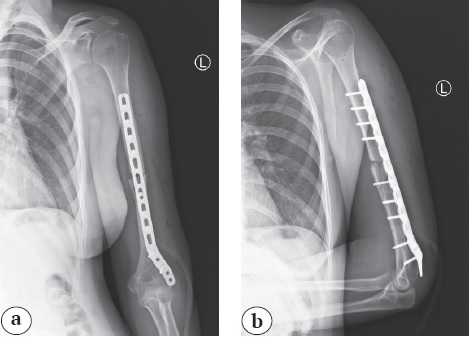

В ходе операции выявлено, что лучевой нерв в средней трети плеча проходит в толще рубцовой ткани, прерывается в месте контакта с верхним из дистальных блокирующих винтов. Имеется рубцовое перерождение нерва на протяжении 4,0 см с концевой невромой проксимального конца (рис. 3).

Рис. 3. Интраоперационная фотография: определяется перерыв лучевого нерва (отмечен стрелками) в проекции дистального блокирующего винта; концевая неврома проксимальной культи нерва

Fig. 3. Intraoperative photo: A break in the radial nerve is identified (indicated by arrows) in the projection of the distal blocking screw; a neuroma at the proximal cult of the nerve